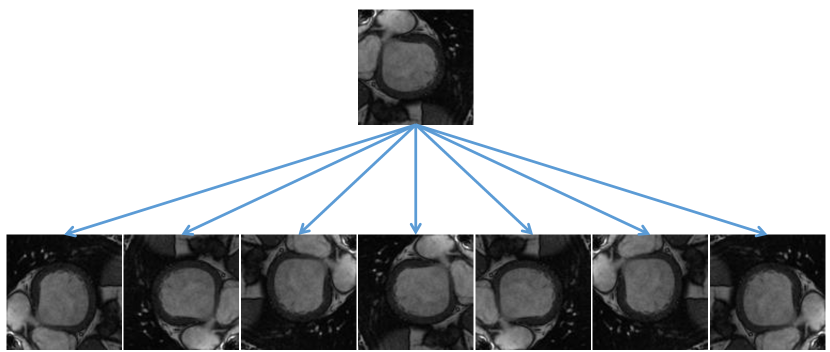

Since the amount of Sunnybrook training samples is small, we perform data augmentation, including displacement, rotation, and flipping, on the training set. First, we use a displacement operation on the training images and each image is translated five pixels in four diagonal directions. Then, we notice that the left ventricle is mostly in the center of image and perform a center cropping. To ensure that all clipped images contain a complete region of interest, we uniformly crop the image to as shown in Figure 5. Meanwhile, the proportion of the left ventricle in the clipped image is relatively large and the class imbalance problem [4] is relieved to some extent.

![]() |

Subsequently, we performed rotation and flipping on the cropped images (as shown in Figure 6), including 90 degrees, 180 degrees, and 270 degrees, as well as horizontal flipping and vertical flipping. In conjunction with the displacement operation, the total number of images we get is equal to 40 times that of original images in the training set.